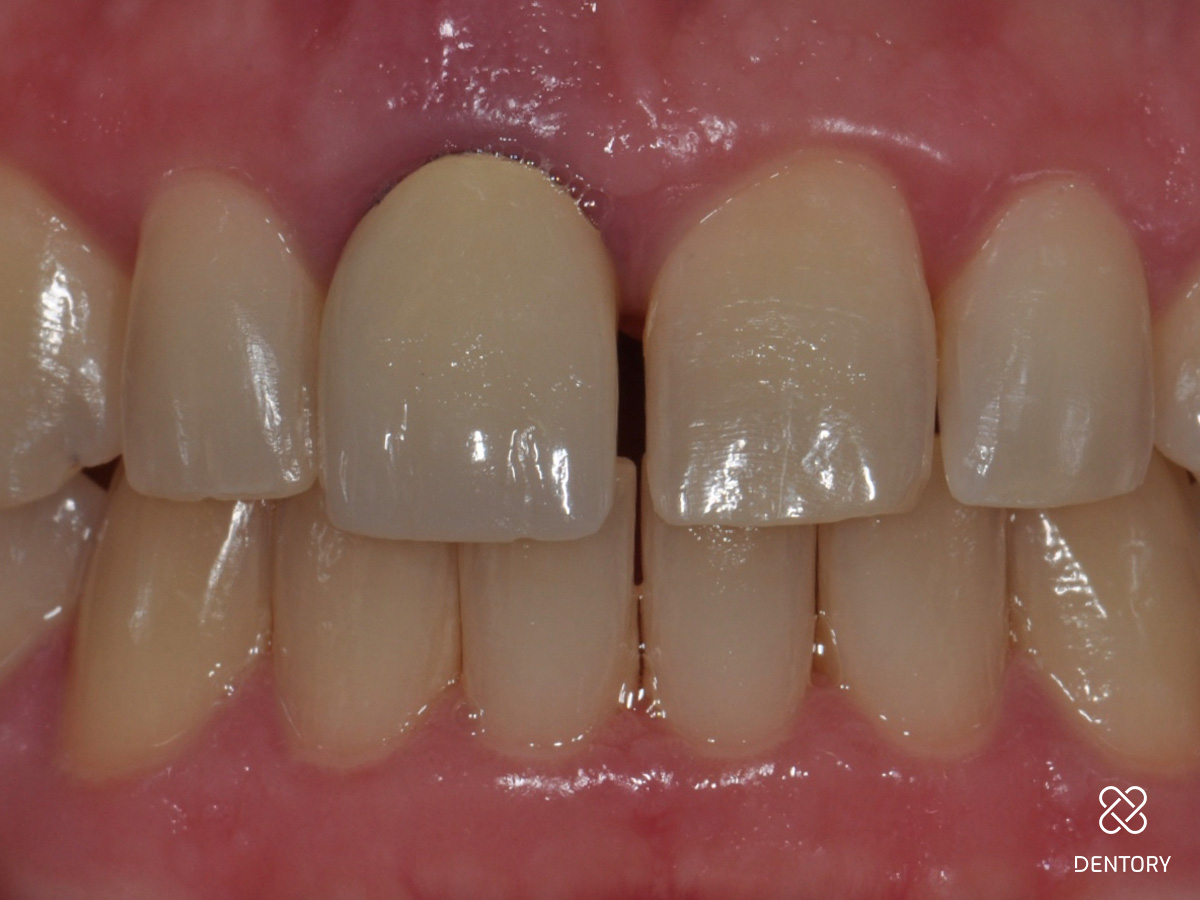

Abbildung 17

Heilung: 8 Wochen Post-OP - frontale Ansicht

Abbildung 18

Heilung: 8 Wochen Post-OP - okklusale Ansicht